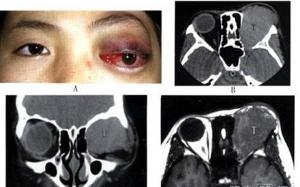

眼眶非霍奇金恶性淋巴肿瘤的分类虽然复杂,临床表现却较为一致,且多见于泪腺区,这是因正常泪腺内有淋巴组织存在的缘故,一侧或两侧眼睑肿胀,下垂,扪及无痛性硬性肿物,眼球突出,并向一侧移位,球结膜水肿,因病变浸润性增生,波及视神经和眼外肌,视力减退经常发生,眼球运动受限,甚者眼球固定,结膜下侵犯,可透过结膜看到粉色鱼肉样肿物,恶性程度较高的肿瘤发展较快,眼睑浸润变硬,遮住眼球,与眶内肿物连为一体,肿瘤发生的年龄和临床表现与淋巴浸润炎性假瘤颇为相似,尤其是需要与泪腺炎型假瘤进行鉴别诊断,眶内恶性淋巴瘤有时伴有其他部位淋巴结肿大,需全身详细检查。

2.CT扫描 多数肿瘤位于眼眶前部并累及包绕眼球,眼外肌或视神经,边界不清楚,形状不规则,增强明显,很少出现骨破坏,但可充满眼眶。

3.MRI 淋巴瘤多位于泪腺,眼睑,也可弥漫侵及眶内软组织,在MRI上TlWI多为中信号,T2WI为高信号,或中高异质信号,增强明显,由于病变呈浸润性增生,可显示包绕眼眶正常结构,甚至充满眼眶。